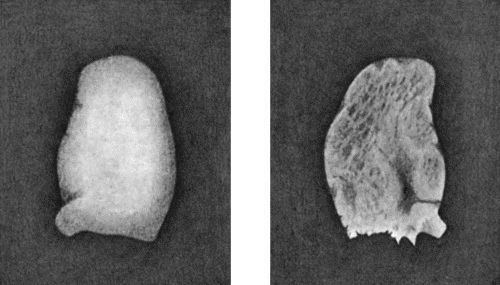

166.Radiogram of Multiple Loose Bodies in Knee-joint 540

167.Loose Body from Knee-joint 541

168.Multiple partially ossified Chondromas of Synovial Membrane from Shoulder-joint 542

169.Multiple Cartilaginous Loose Bodies from Knee-joint 543